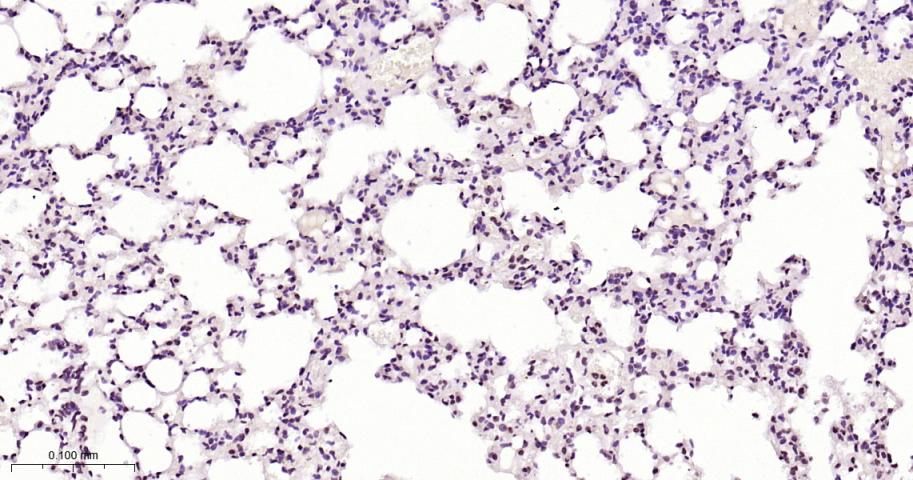

| IHC-P | Human, Mouse, Rat | 1:100-500 | |